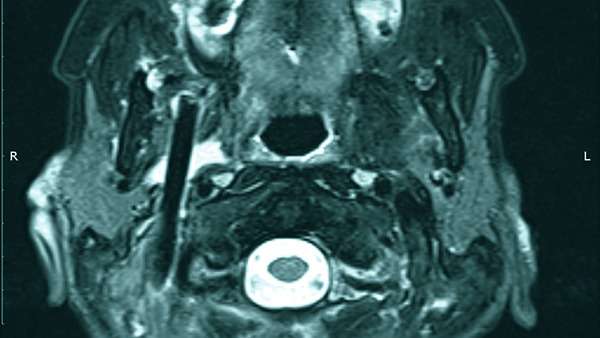

LifestyleՀամբուրգի 65-ամյա բնակչուհին դիմեց բժիշկներին՝ ասելով, որ չի կարողանում գտնել ատամները լվանալու ժամանակ կորցրած էլեկտրական խոզանակի կտորը: Բժիշկները նախ հետազոտեցին կնոջ ստամոքսն ու աղիները, բայց ոչինչ չհայտնաբերեցին և նրան ուղարկեցին տուն: Բայց մի քանի օր անց կինը կրկին դիմեց հիվանդանոց՝ գանգատվելով, որ ոչինչ չի կարողանում ուտել: Դիմածնոտային վիրաբույժը կնոջ բերանի խոռոչի փափուկ հյուսվածքներում 6 սմ երկարությամբ օտար առարկա նկատեց: Պարզվեց, որ դա հենց ատամի խոզանակի ջարդված կտորն էր: Վիրահատությունից հետո մի քանի օր անց կինը դուրս գրվեց: